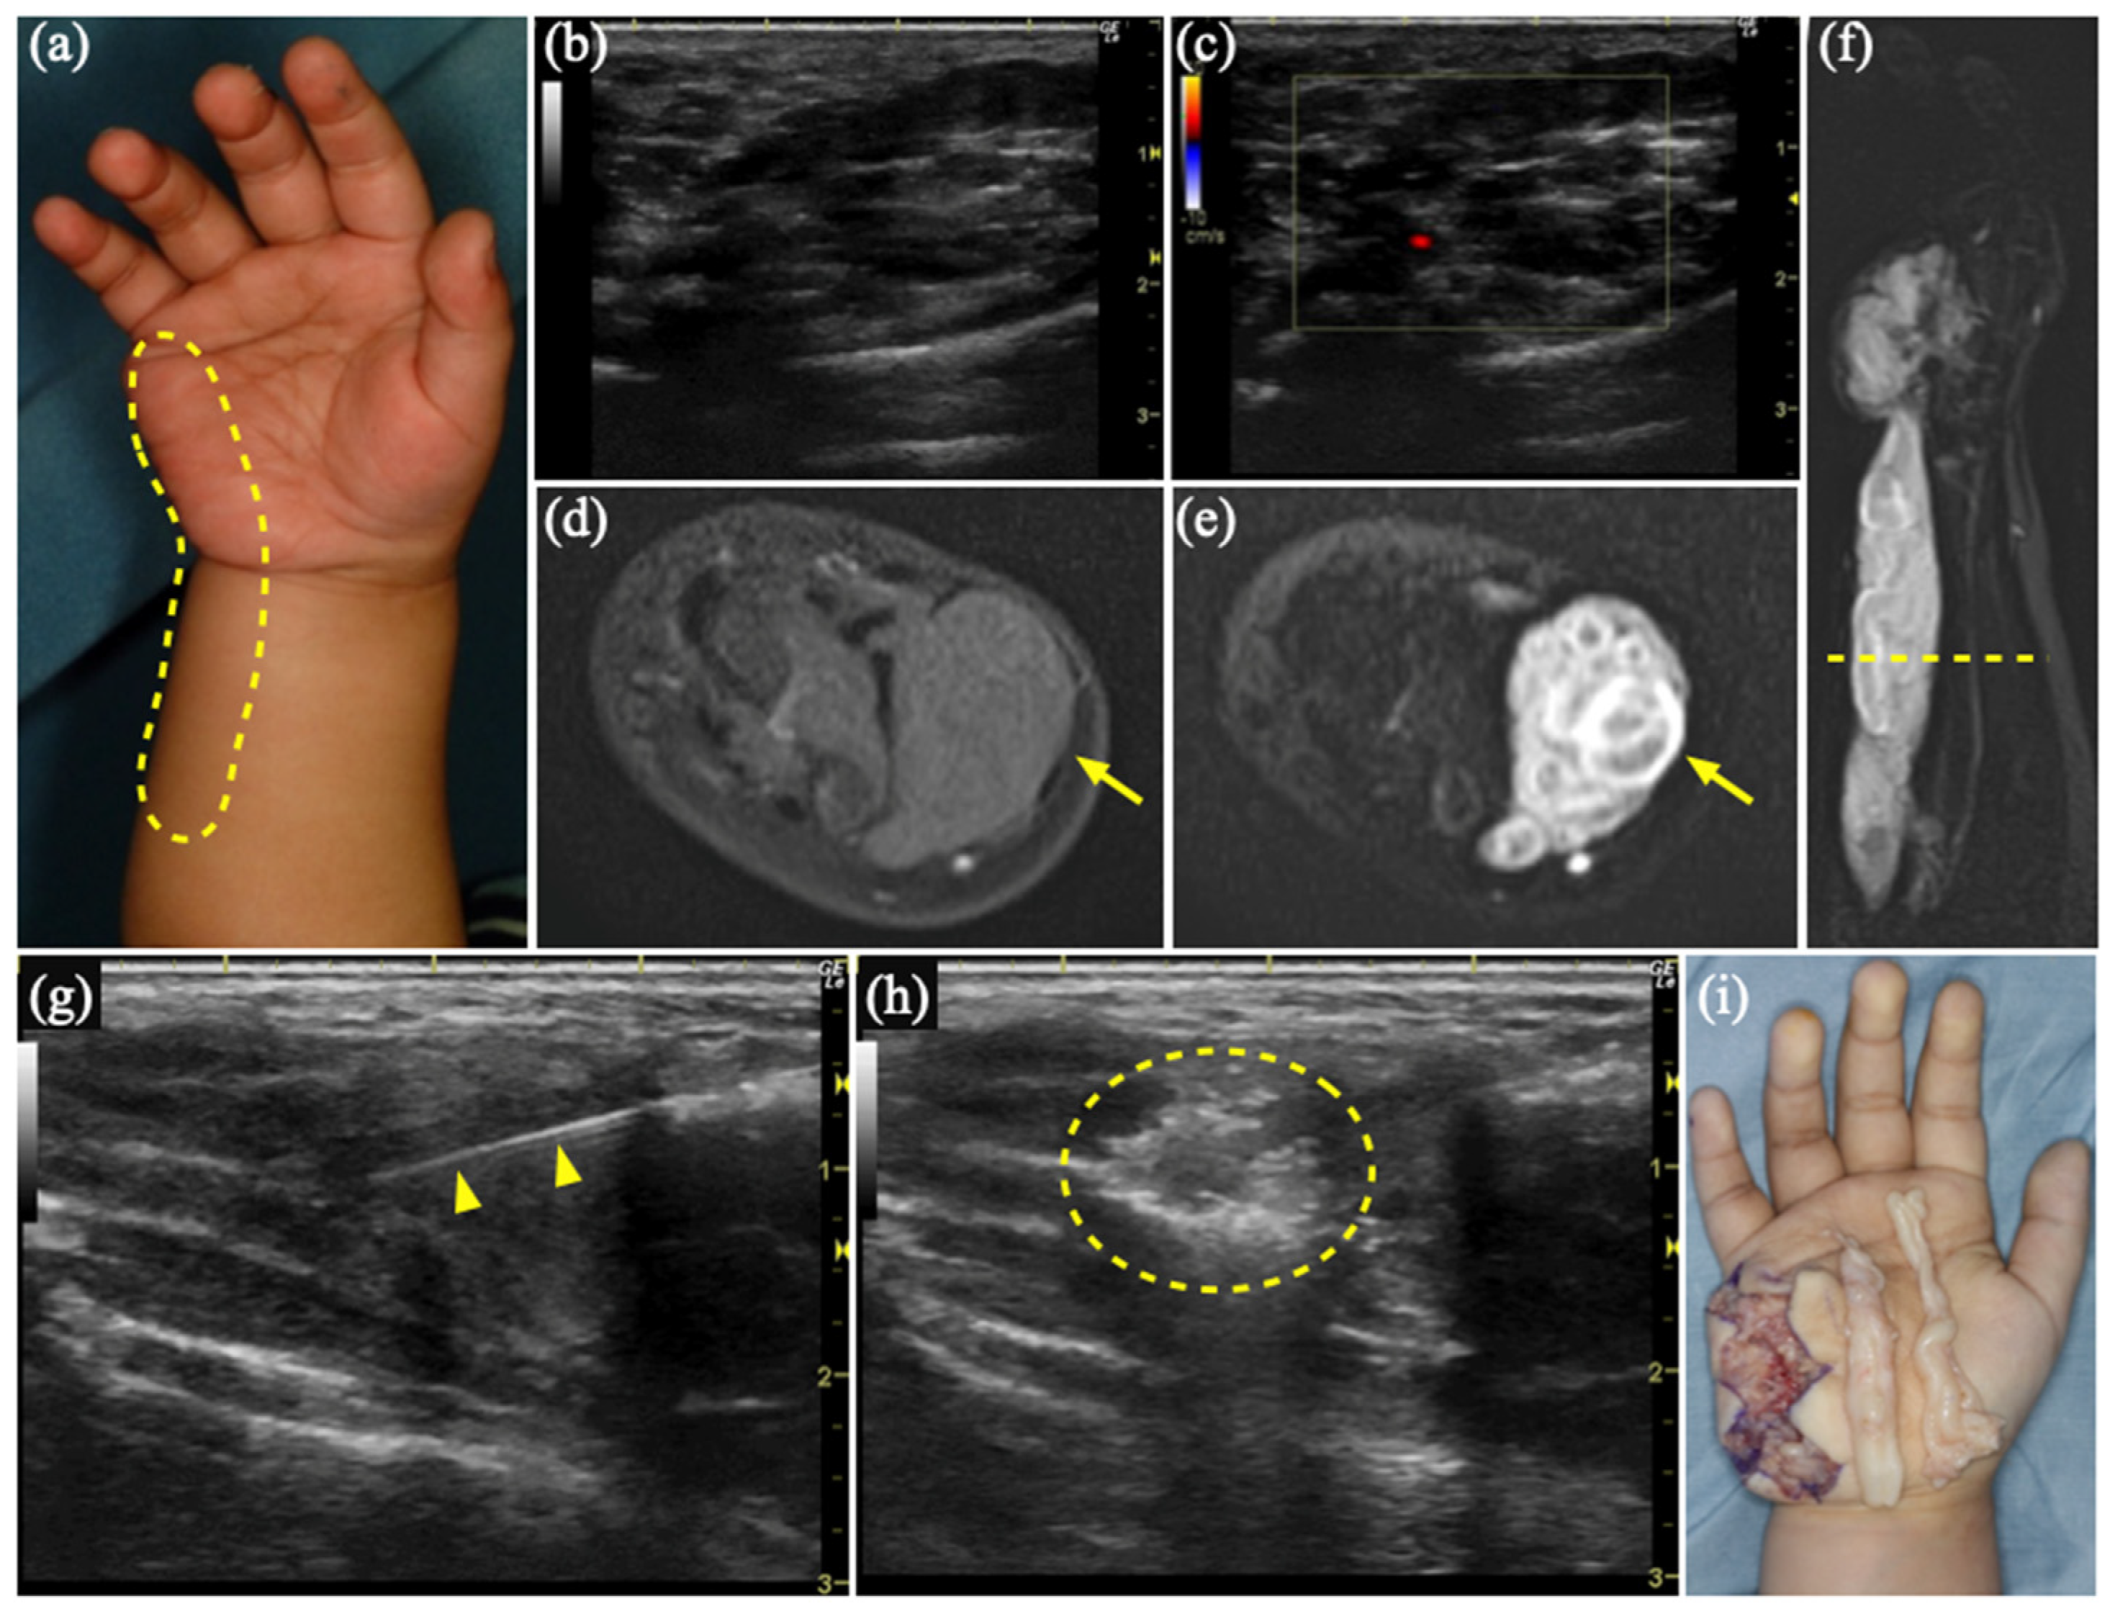

3.2. Case 1

3.3. Case 2

| 1 | 2 | F | Rt hand, forearm | VM | US, MR | Sc, 4 times | Schwannoma | 1893 |